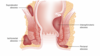

What is the diagnosis? Describe the findings

1. Gallbladder with gallstones 2. Thickened gallbladder wall 3. pericholecystic fluid Together with a sonographic Murphy sign, these findings constitute the sonographic findings in cholecystitis.